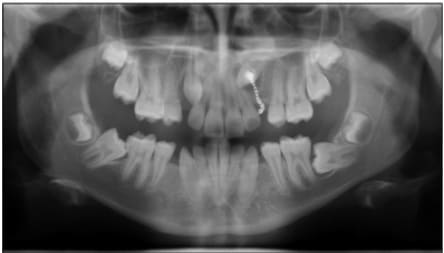

Si joint de illustration tiré de publication, juste pour montrer a notre amis alapex que si pour une raison X ou Y ont veut récupérer cette 8 c'est faisable, compliqué cher mais faisable.

J'ai complété le schéma que tu avais posté plus haut dans le plan sagittal, fais comme ça dans un plan frontal au niveau 48 et tu verras.

Daniel

Sch ma seespan p9lbl9 - Eugenol